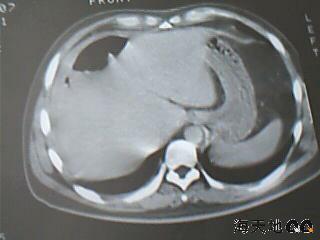

男 32y 外伤后一月余,现 t38.5,肝区隐痛。

右肝膈顶区液气平面.右膈肌增厚改变,病灶下部层面呈半月形延伸于肝表面.且于横结肠无明确密度切关系.

结合临床症状;考虑膈下脓肿.建议薄层矢状重建进一步证实.

鉴别;1,膈疝;2,间位结肠.

右隔肌与肝顶之间隙有长气液平,其下散在点状气体影,右侧腹膜局限增厚。考虑右膈下脓肿。

考虑右膈下脓肿。病灶不在肝内,位于肝外膈下;病灶下方的层面无结肠影与之相连。

右膈肌增厚,肝膈间见条状低密度影内可见积气影及宽大液平面,并未见与结肠相连。因此考虑膈下脓肿。